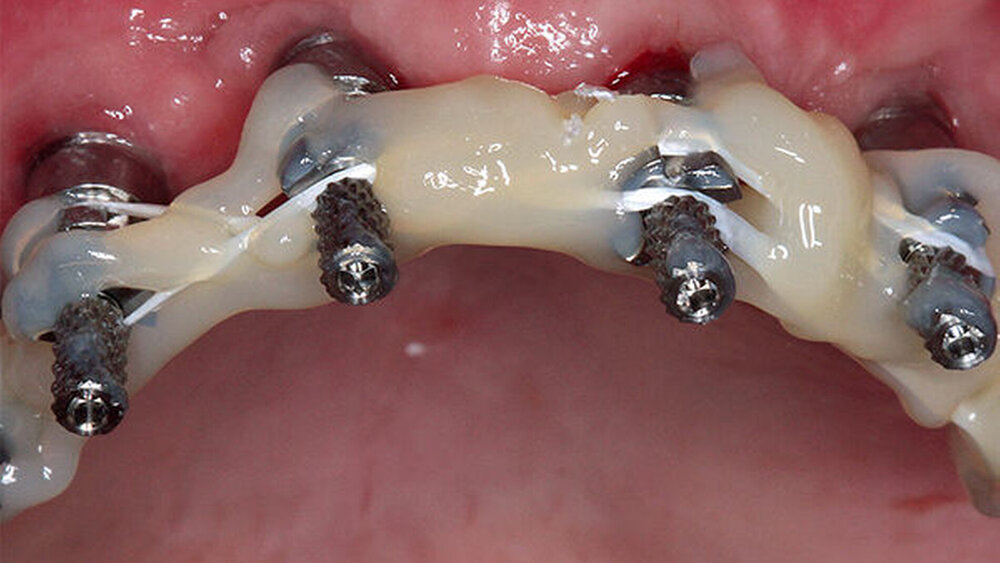

Buhtz: Korrekt, die Voraussetzung ist lediglich die Generierung von DICOM- und STL-Daten, die im Computer exakt übereinandergelegt werden können. Dann erfolgen die Behandlungsplanung wie gewohnt mit ICX-Magellan und die provisorische ‧Versorgung mit dem präfabizierten, chairside hergestellten verklebten PMMA-Provisorium (ICX-‧Smile‧bridge). Seit eineinhalb Jahren arbeiten wir zudem mit dem medentis Fräszentrum Denta5 zusammen.

Buhtz: Wir schicken die Scan-Daten, ein Wax-up und ggf. das Modell mit den Laborimplantaten an das medentis-Fräszentrum und erhalten zwei Tage später die verschraubte Unterkonstruktion. Denta 5 gibt es bereits seit einigen Jahren. Doch erst seit wir einen eigenen Modellscanner haben, stellen wir verschraubte Brücken auf diese Weise her. Jetzt habe ich eine Zahntechnikerin, die damit gut klarkommt. Full-arch-Versorgungen sind bei uns allerdings nicht das Tagesgeschäft, wir machen das vielleicht zehn- bis zwanzigmal pro Jahr. Unsere Patientenklientel ist in der Regel nicht zahnlos.